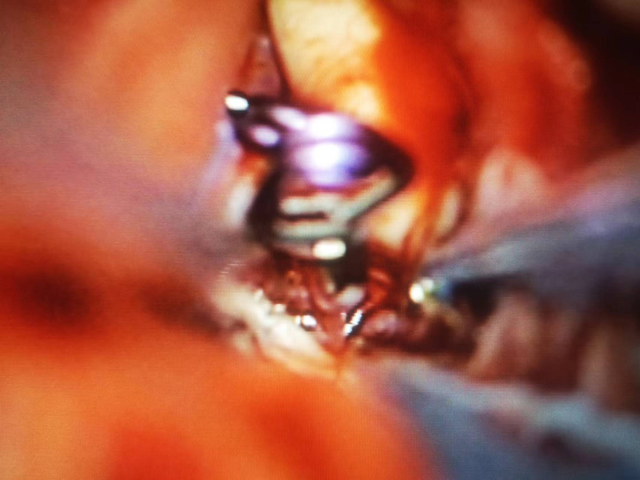

术中,在显微镜下仔细地穿过细小的烟雾血管,拆除两枚“炸弹”后全身而退,又进行血运重建手术,以期让这些烟雾血管在不远的将来也逐步消退,减少再次出现脑血管意外的几率。

术中动脉瘤夹闭完全

荧光造影未见动脉瘤显影